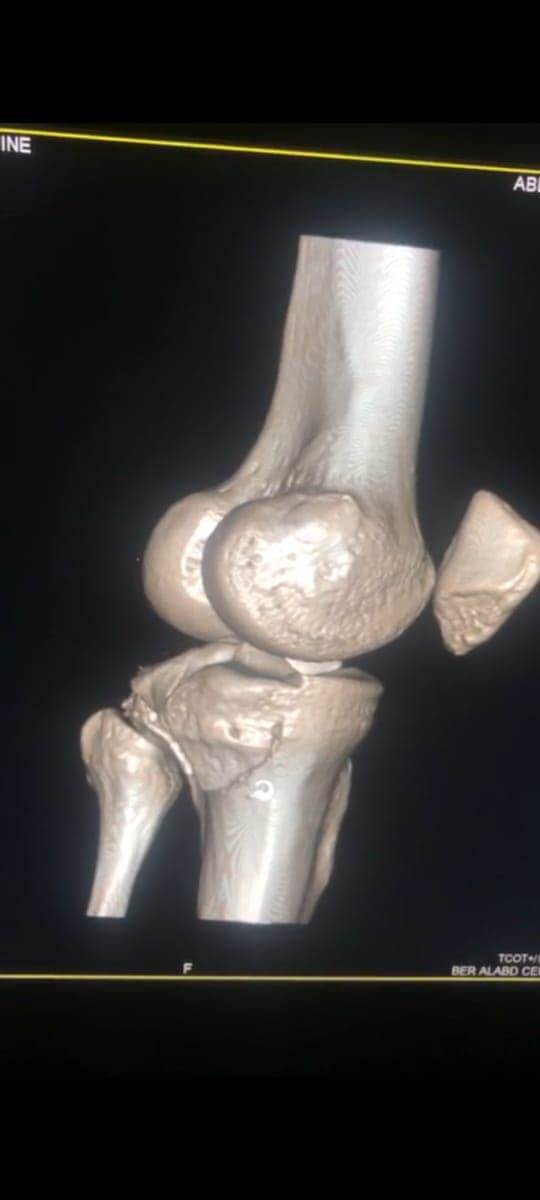

مشيرًا الى أن ذلك النوع من الكسور يكون قريبًا جدًا من الأعصاب والأوعية الدموية الرئيسية للساق والتي توجد خلف مفصل الركبة.. حيث تم الوصول الى الكسر وإعادة بناء سطح المفصل وتثبيته باستخدام شريحة ومسامير وأسلاك معدنية باستخدام جرح ٧ سنتيمترات خلف الركبة واستخدام مسامير جانبية مجوفة بدون فتح لتثبيت الجزء الخارجى من سطح المفصل، وتم الاطمئنان على الأوعية الدموية قبل إفاقة المريض، وبعد تمام الإفاقة.. تم الاطمئنان على الأعصاب والأوعية للمريض.

وأضاف أنه نظرًا لقرب هذا الكسر من سطح المفصل تم عمل أشعة مقطعية بعد الجراحة للتأكد من جودة بناء المفصل وعدم وجود أى بروز للمسامير داخل المفصل، وجارٍ تحضير المريض لعمل رنين مغناطيسى لتحديد الأربطة الداخلية والخارجية للركبة التي ستحتاج لإعادة بناء بالمنظار.